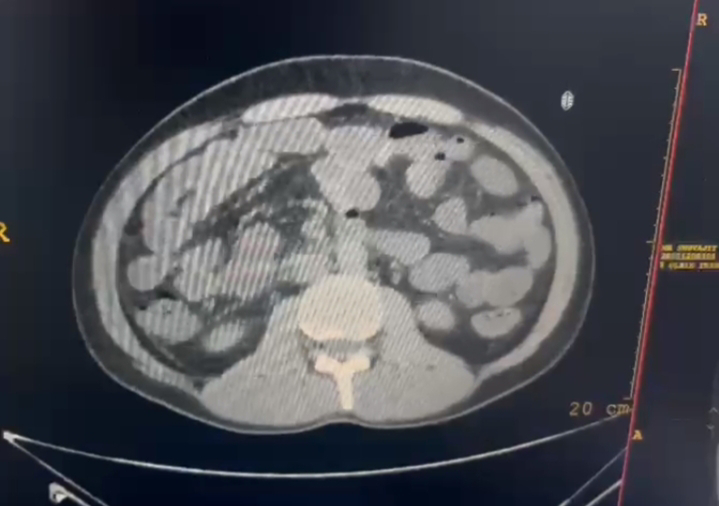

"In August 2022 ,the patient had an episode of abdominal pain and vomiting, for which he was admitted to a hospital. A CT of abdomen was performed and a lump was found in the pancreas. On further investigation, it was found that the lump was not cancerous. The patient was given symptomatic treatment and discharged when he was stable."

1) CE CT ( Contrast Enhanced CT):